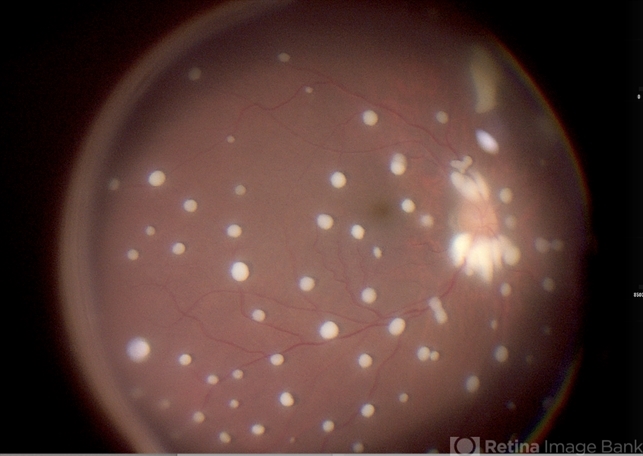

- 57 year diabetic female , was treated as a case of recurrent vitreous post cataract surgery. Patient was posted for vitrectomy 3 months post cataract surgery. Intra-operatively, multiple yellowish colonies were seen all over the posterior pole were seen, which were later found to be Aspergillus colonies.